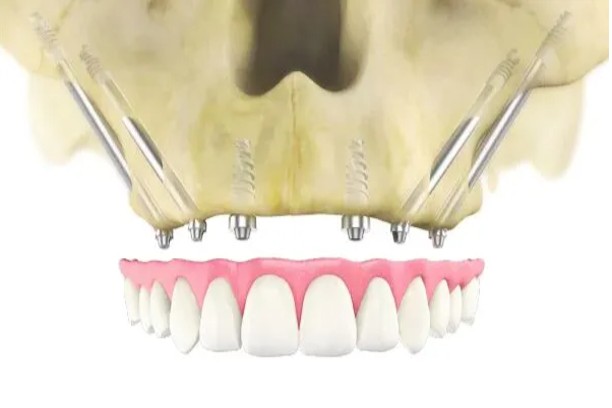

Zygomatic / Pterygoid Implants

Anchored in the cheekbone for patients with limited upper jaw bone.